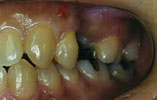

CASE5

下の奥歯3本を失った場合 機能的回復

下の奥歯3本欠損で従来取り外し式の部分入れ歯が入っていましたがインプラントを2本埋入し、固定式のブリッジを装着しました。